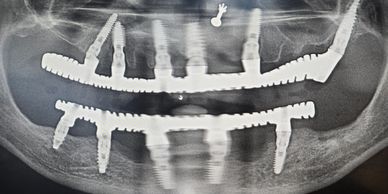

Advanced immediate loading protocols mean you won't spend time without teeth. Temporary restorations provide immediate function while your permanent smile is being crafted.

Our systematic approach and laboratory capabilities ensure that your treatment stays on schedule, with most patients completing their transformation within a week.

Treatment protocols and infection control strategies developed as per global standards and refined over thousands of cases ensure consistent, excellent outcomes.